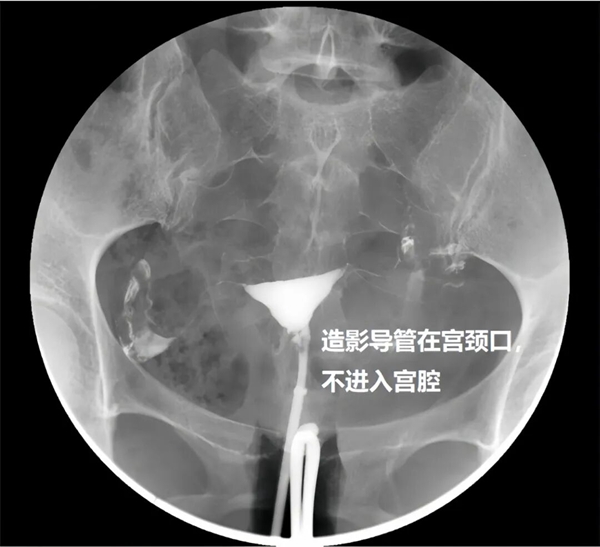

与传统无痛技术不同,该技术并非依赖麻醉,而是通过检查方式的革新实现无痛体验。无痛子宫输卵管造影是在传统造影基础上,采用新型专用导管,无需插入宫腔,仅在宫颈外口利用外界压力即可完成含碘造影剂的注入,从根本上避免了导管对宫腔的刺激。

其二,精准成像,诊断更可靠。导管不进入宫腔,避免了宫腔内遮挡与阻碍,能更清晰、准确地呈现子宫腔形态与输卵管通畅情况,为临床诊断提供更精准的影像依据;